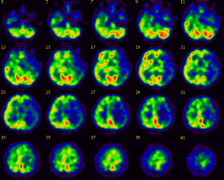

治療前の脳血流画像

画面に向かって左側の脳がおおよそ緑色で表示されているのに対し、右側の脳は青色で表示されています。

青色の表示は、血流が低下していることを示しています。